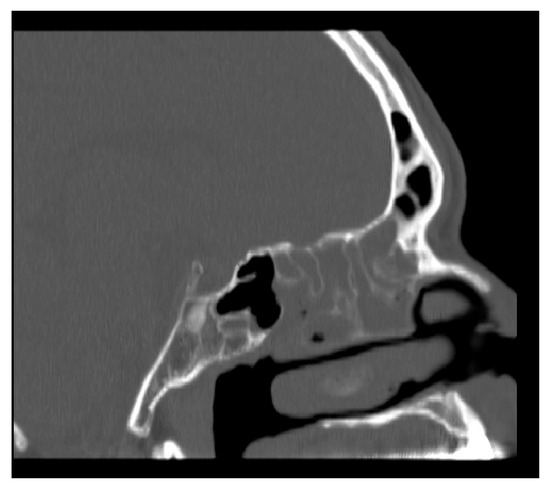

2.1. Method of NasoLens Safety and Effectiveness Simulation

We aimed to assess NasoLens’ ability to safely and effectively navigate the nasal canal without causing injury or discomfort. To simulate the nasal anatomy, a range of CT scans was obtained from a hospital. These scans were selected to capture various anatomical variations and ensure that the test models represented a diverse patient population, as shown in Figure 1. Using these scans, accurate 3D digital models of the nasal passages were generated, as shown in Figure 2. The digital models were subsequently converted into physical representations using 3D printing technology, allowing us to evaluate NasoLens’ ability to reach key target locations.

Figure 1. CT scan of nasopharynx.